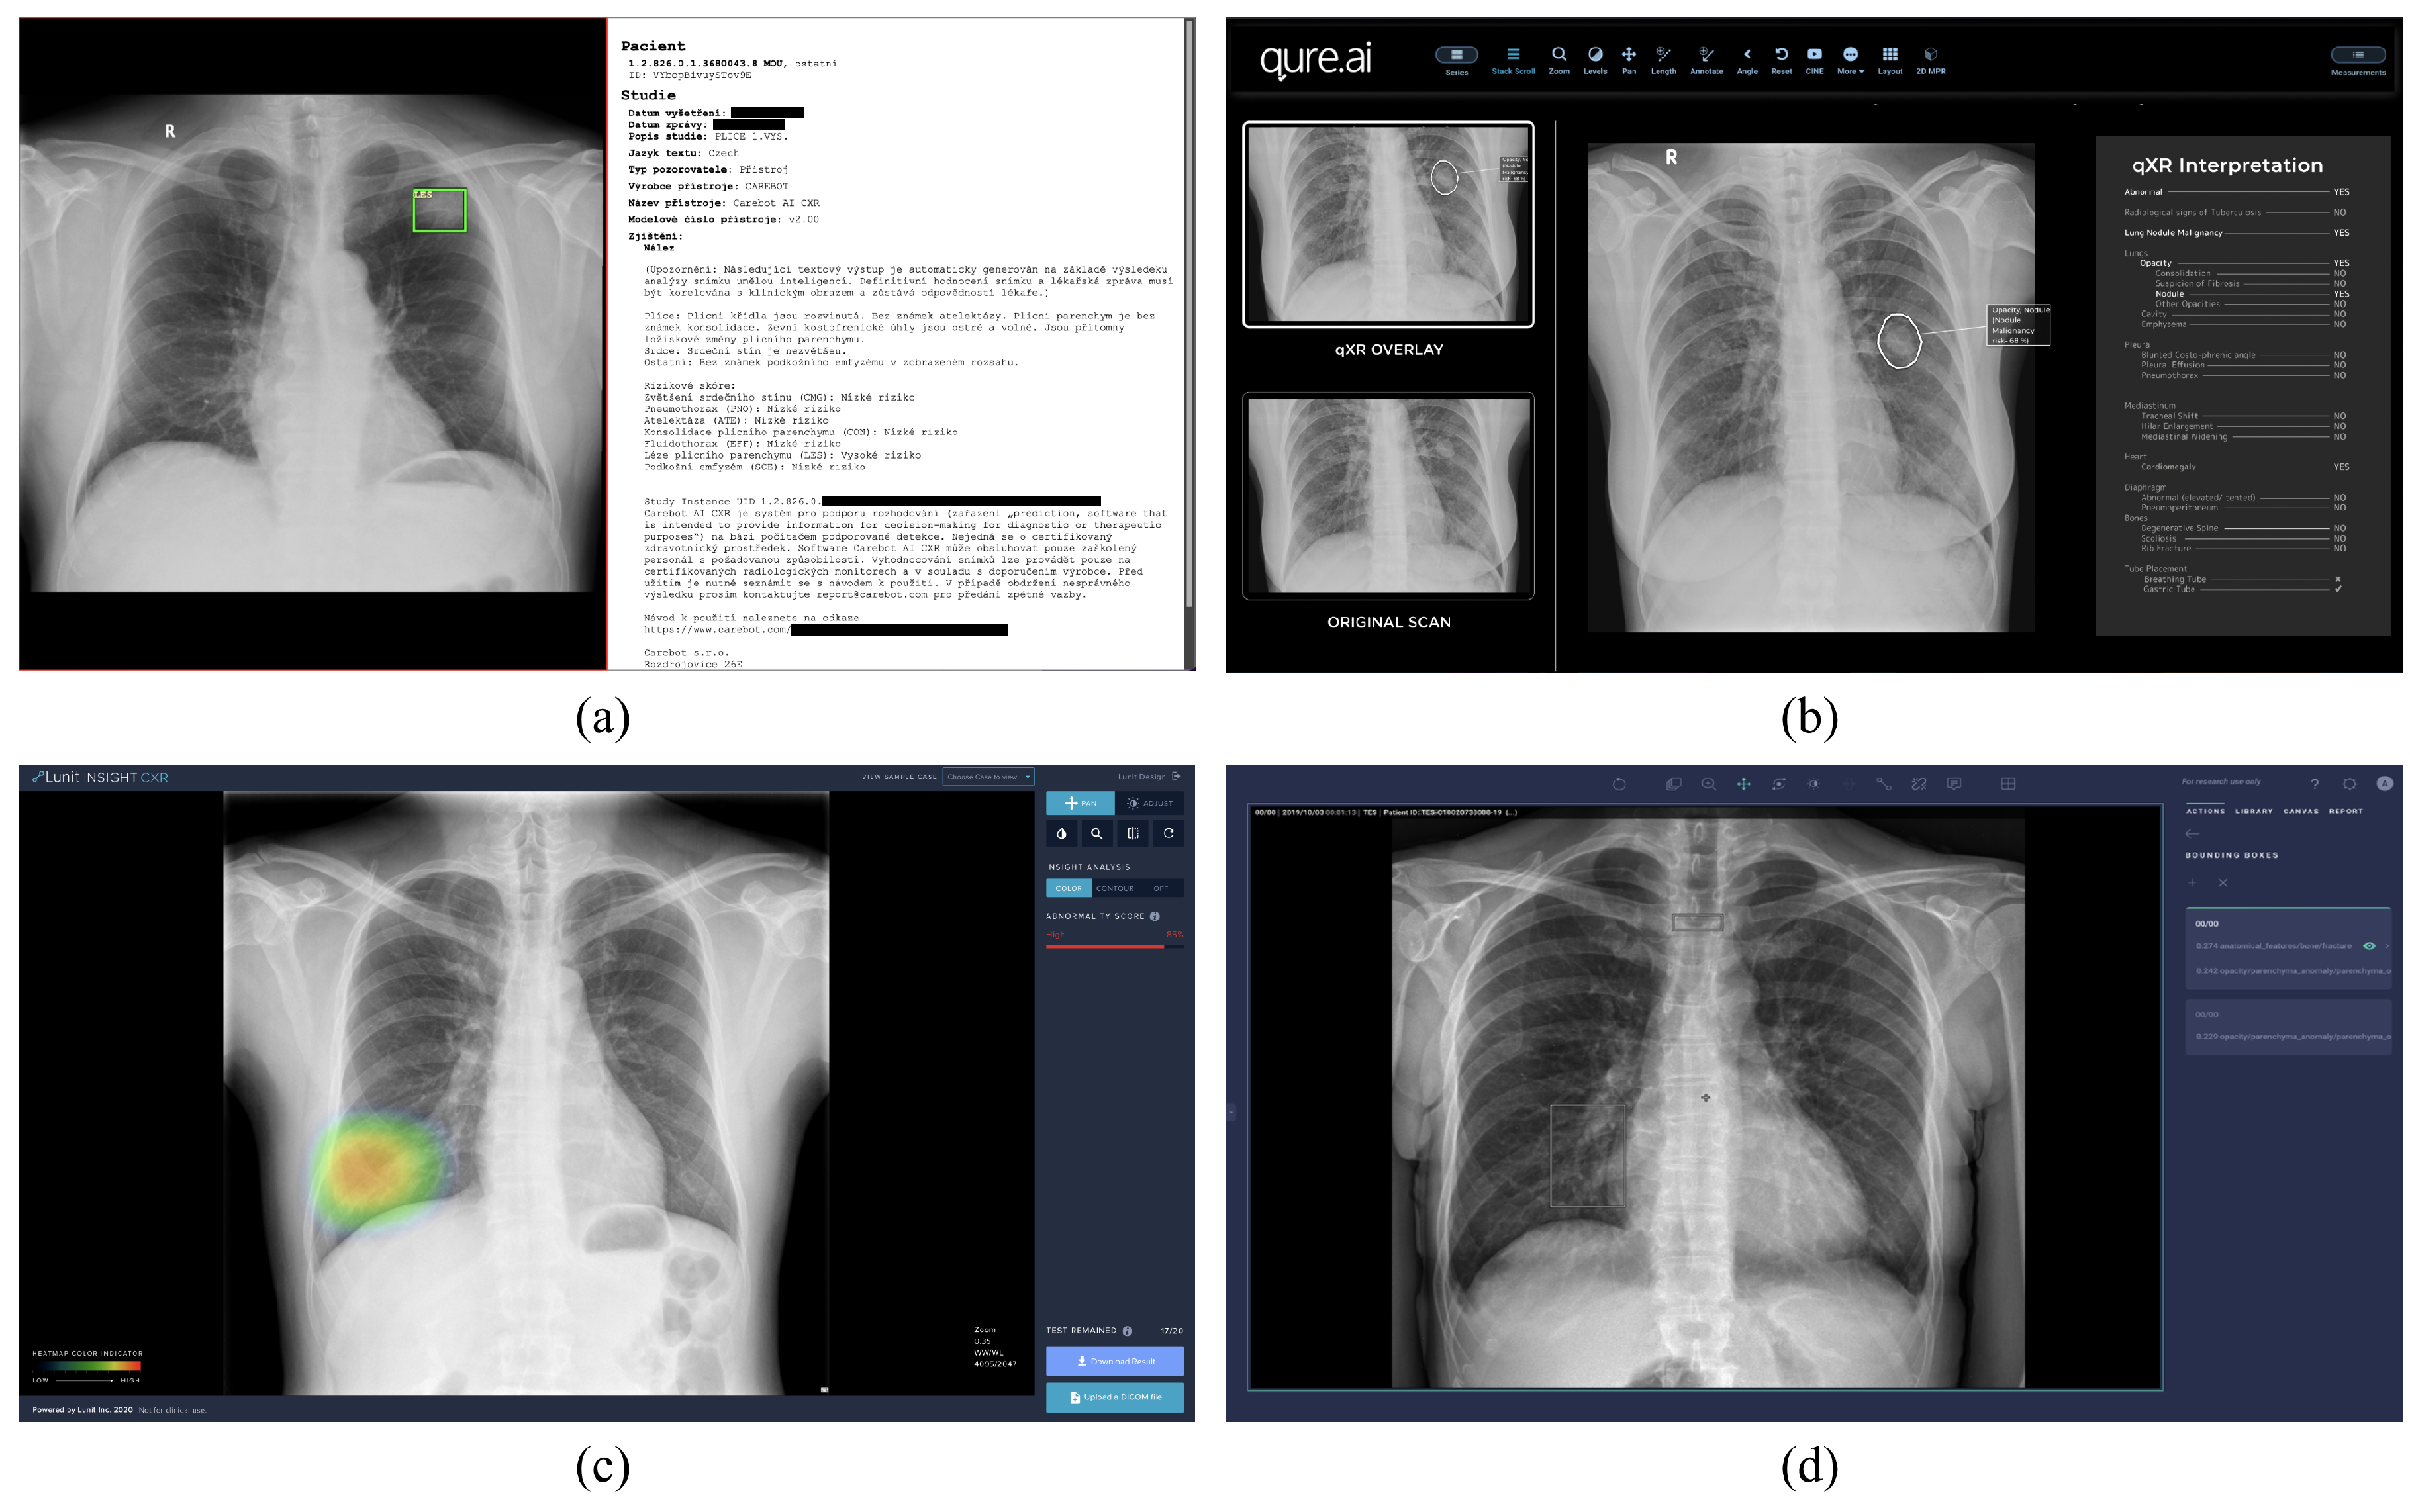

3.1. Software

3.1.3. Communication Protocol